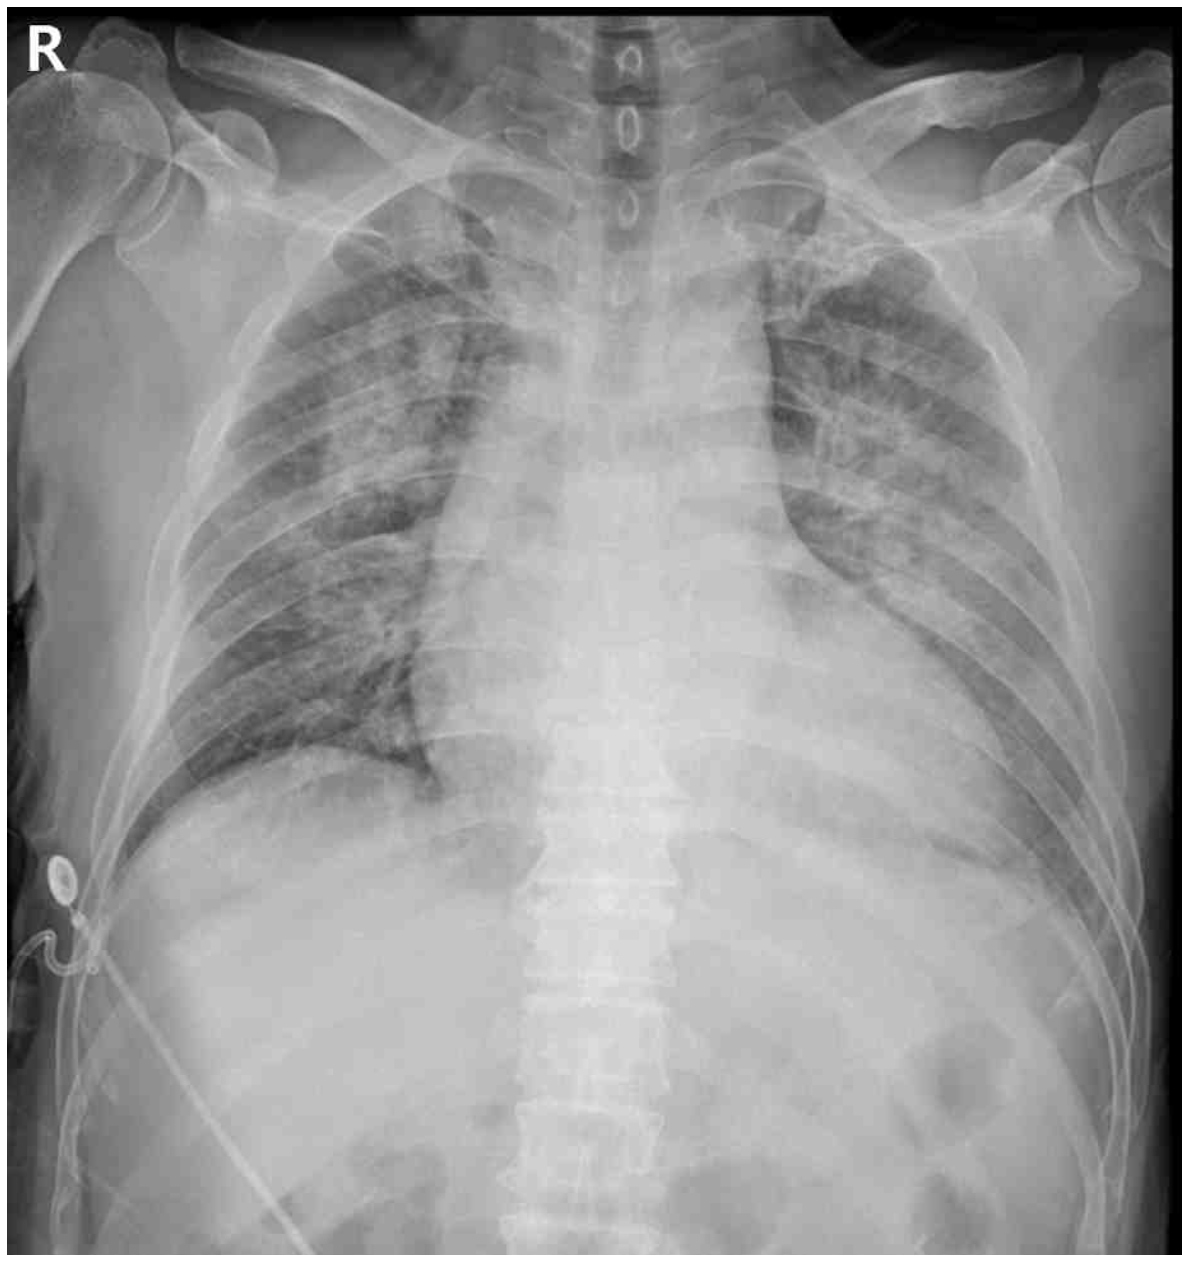

55세 남자가 1일 전부터 숨이 차서 병원에 왔다. 7일 전부터 열이 나고 전신 쇠약감을 느꼈고, 1일 전부터 숨도 차기 시작했다고 한다. 혈압 107/55 mmHg, 맥박 102회/분, 호흡 26회/분, 체온 38.3°C이다. 복장뼈 왼쪽 3번째 갈비사이공간에서 확장기 심잡음이 들린다. 가슴 X선사진과 심전도이다. 혈액검사 결과는 다음과 같다. 검사는?

CXR: Cardiomegaly, pulmonary edema

• CXR 상 cardiomegalypulmonary edema가 확인되며 혈액검사상 BNP가 상승했으므로 HF에 의한 호흡곤란임을 알 수 있다.